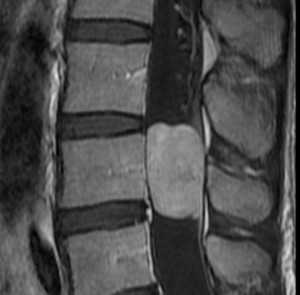

(Слева) Сагиттальный срез, Т2-ВИ, 15-летний пациент: жировая перестройка костного мозга, ограниченная зоной вокруг центральных дренирующих вен каждого позвонка. Остальная часть тел позвонков заполнена красным костным мозгом. Подобная МР-картина типична для пациентов молодого возраста.

(Справа) На сагиттальном Т1-ВИ 50-летнего пациента определяется смешанная картина «ткани в горошек», характеризующаяся перемежающимися друг с другом участками красного и желтого костного мозга. Жировой костный мозг обычно локализуется вокруг дренирующих вен и вблизи замыкательных пластинок. Красный костный мозг характеризуется аналогичной или несколько повышенной по сравнению с мышцами интенсивностью сигнала.